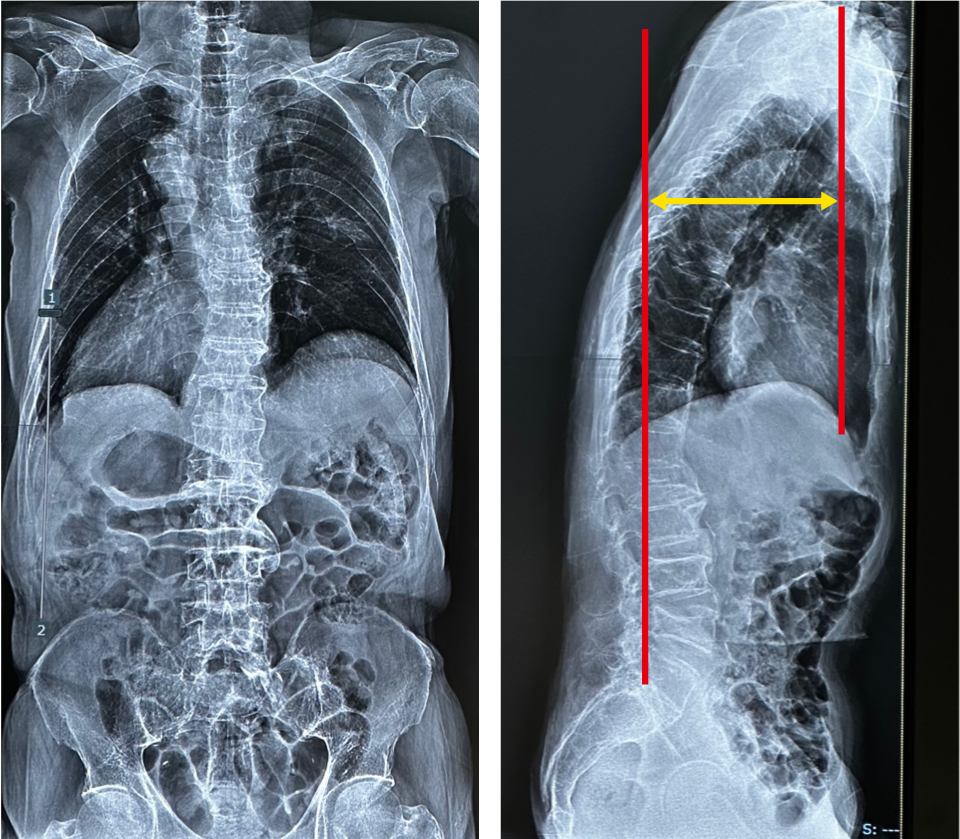

変性後側弯症

59歳女性。徐々に姿勢の悪化と共に腰痛、左下肢痛が増悪してきたため受診。変性後側弯症の診断で手術方針となった。第7頸椎から下ろした垂線と第1仙椎後上縁の距離Sacral Vertical Axis(SVA)は100mmであり矢状面バランス不良を認める。